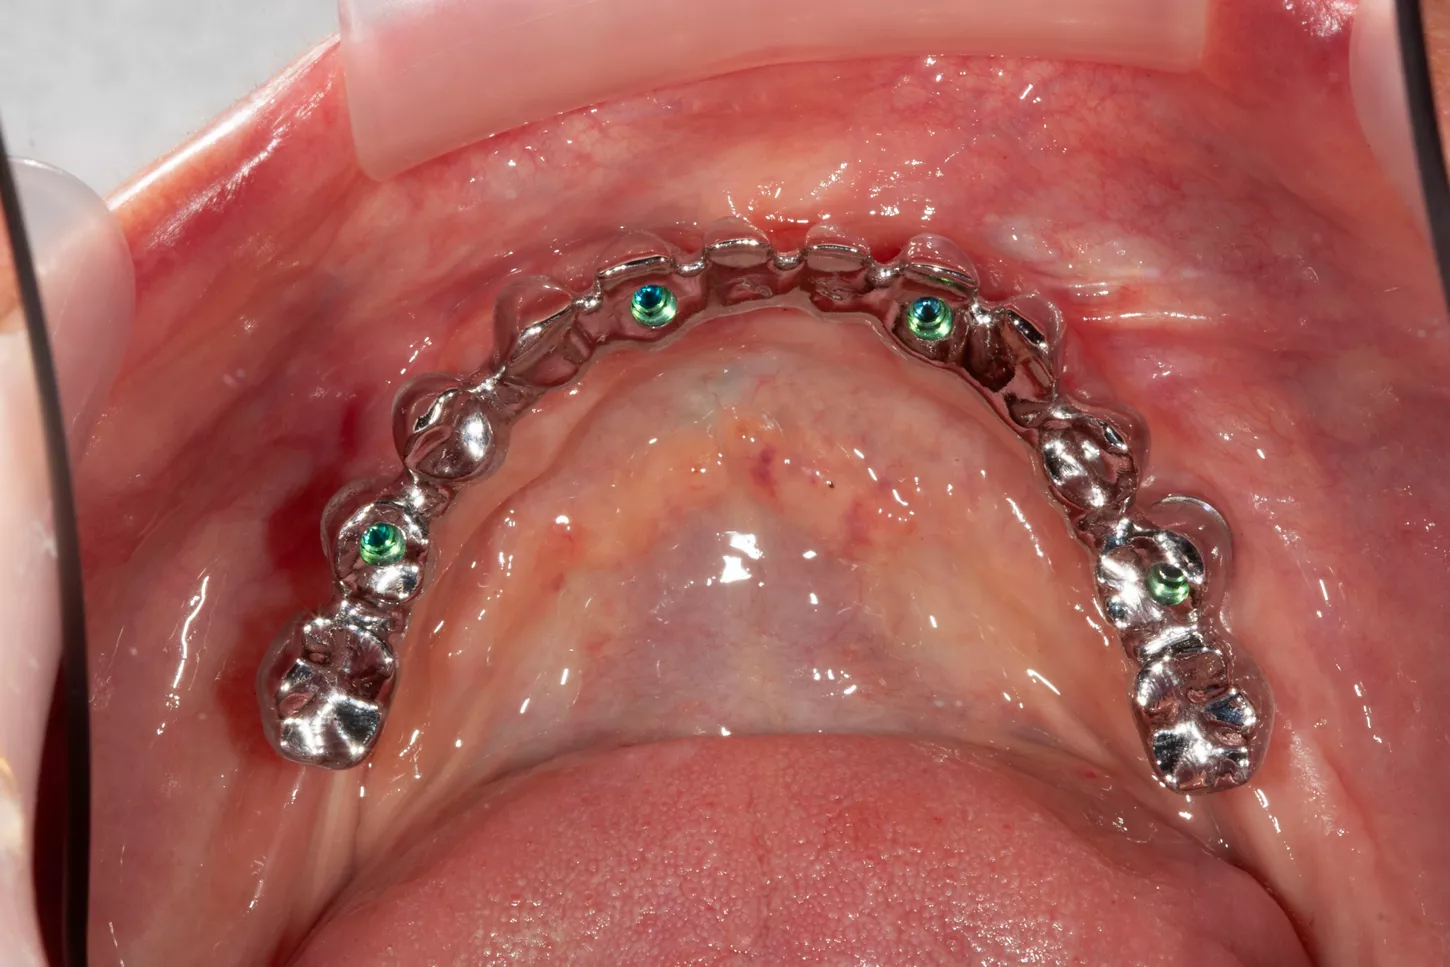

13. Occlusal pictures of healing around the implants at 3 months follow-up upon removal of the provisional prosthesis.

14. Positioning of the transfers in the lower jaw for impression.

15. The framework structure for the lower jaw ensures a precise fit on the 4 Axiom X3® TL implants.